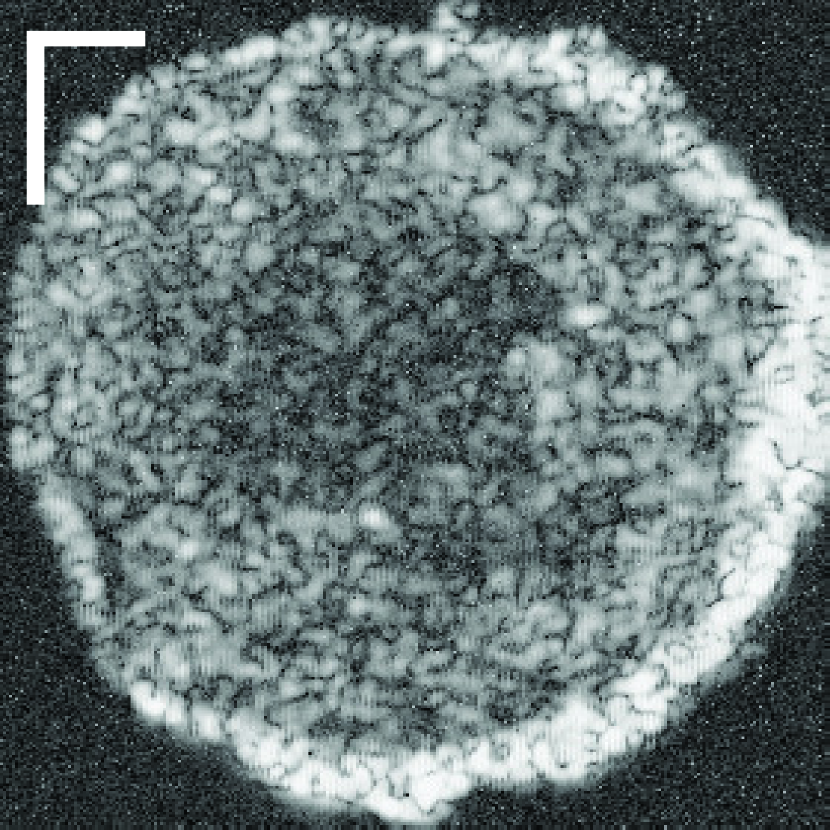

Figure 10: (a) Target HFU image. (b) Manual segmentation result. (c) The result of RFC+STS-LS. (d) The result of NGC with depth-dependent profiles. (e) The result of proposed method without global energy (one round of GC-LAE). (f) The result of proposed method with global energy (two rounds of GC-LAE).

Figure 10 displays the segmentation results of four typical LNs to illustrate the advantages and disadvantages of the three different segmentation methods. RTS-LS with RFC and NGC with depth-dependent profiles segment LNP mainly by intensity information, and GC-LAE-based methods segment LNP mainly by the intensity similarity of local regions.

IV-A1 LNs with Clear Boundary and Consistent Intensity Distributions

The top LN has clear boundary and consistent intensity distributions. Therefore, all four segmentation methods can obtain satisfactory results. However, RFC+STS-LS may converge to a false local minimum during deformation as shown in the top figure of Figure 10(c). In contrast, the GC-based approach can avoid this kind of error.

IV-A2 LNs with Clear Boundary and Non-homogeneous Acoustic Attenuation

As discussed in introduction, depth-dependent profiles may not perform adequately in the presence of inconsistent profiles, where the intensity of voxels within the same depth in one object may not be consistent. To illustrate this point, the second row of Figures 10(c) and 10(d) show the segmentation result of RFC+STS-LS and NGC with depth-dependent profiles, respectively. Comparing these results to the manual-segmentation result in Figure 10(b), we can identify a fat region on the left mislabeled as LNP because the fat in the right region of the image at the same depth is brighter than the fat in left. In this case, NGC with depth-dependent profiles and RFC+STS-LS were unable to correctly segment the fatty region on the left. Because the contrast between LNP and fat is strong enough on the left side of the LN, GC-LAE was able to find the boundary correctly (Figure 10(e) and 10(f)) independent of whether the global-energy term is used.

IV-A3 LNs with Blurry Boundary and Low Intensity Difference between LNP and the Fat

GC-LAE determines a boundary based on the similarity of local intensity distributions. Therefore, it may not be able to find the boundary correctly when the boundary is blurry. In the third LN of Figure 10, the boundary between LNP and the fat in middle is extremely blurry and the intensity difference between them is low. In this case, GC-LAE cannot find the boundary correctly even with global energy because of insufficient contrast, but RFC+STS-LS and NGC with depth-dependent profiles were able to provide better segmentation results according to intensity distributions. RFC+STS-LS obtain the best results in this case by updating intensity distributions gradually with deformation.

IV-A4 LNs with Blurry Boundary and High Intensity Difference between LNP and the Fat

The bottom row in Figure 10 shows a transverse slice of an LN with a “blurry” boundary at the upper left corner, and the intensity of the fat on right is much brighter than LNP. In this case, RFC+STS-LS remained at a false local minimum during the segmentation of this LN. NGC with depth-dependent profiles performed better, but it was adversely influenced by the blurry boundary. GC-LAE without global information also incorrectly segments some bright voxels of LNP as fat. In this example, GC-LAE with a global-energy term has the best performance. Using the additional information provided by the depth-dependent profiles, the resulting boundary nearly matches the true boundary.